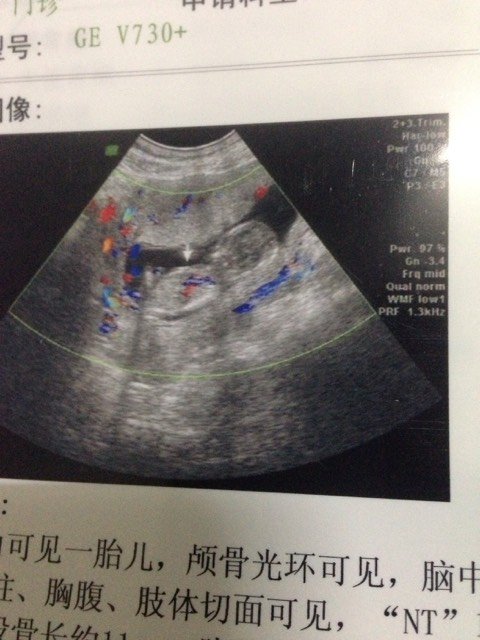

谁知道看男孩和女孩告诉一下吧!一胎是儿子现在想个女儿啊! 谁知道看男孩和女孩告诉一下吧!一胎是儿子现在想个女儿啊! 点击展开 afx118 2014-12-29 00:56 为您推荐: 其他回答 我也想要女儿 艺雪之恋 2014-12-29 19:05 看不准的。 奇葩妹子闯天涯 2014-12-29 10:01 祝宝妈好孕 Love smile giggle 2014-12-29 09:33 祝宝妈好运 132*****006 2014-12-29 08:43 看不出。。 An娜 2014-12-29 07:56 加载更多 相关问题 我第一胎是女儿,我这是第二胎了,是女孩还是男孩呀帮忙看一下谢谢啦! 刚怀孕的时候梦见自己生了个儿子 这几天又梦见自己生了个女儿 宝贝不管男孩女孩我都喜欢 胎梦梦到生儿子的,又梦到过生女儿的,到底男孩女孩啊